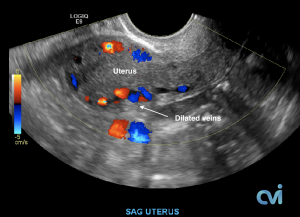

The abnormal veins dilate and cause varicose veins around the ovary and uterus because the valves don’t work properly. Blood flow is in the wrong direction, pooling in the veins and causing them to enlarge.

PCS can be diagnosed by Ultrasound or CT of the Abdomen and Pelvis.

Ultrasound examination is the least invasive study and can identify enlarged veins around the uterus and pelvis. However, sometimes the veins in the pelvis are difficult to see or can be missed if the technician is not specifically looking in the right area.